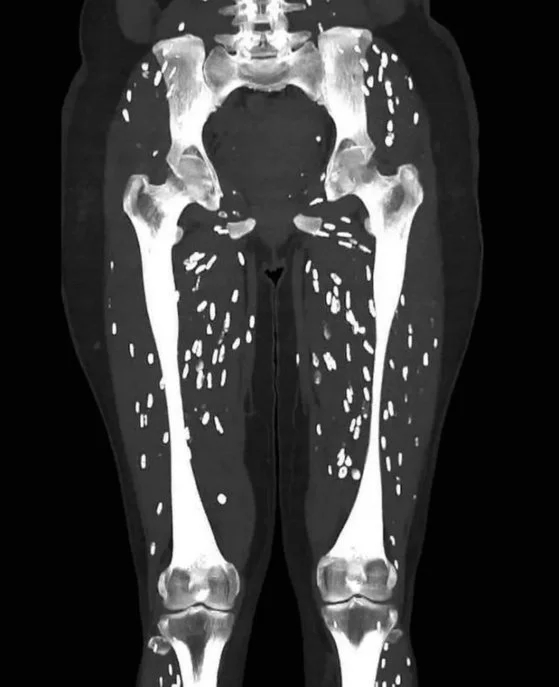

덜 익은 삼겹살 이래서 위험…몸 속 '쌀알' 가득, 충격의 CT

미국의 한 대학병원 의사가 덜 익힌 돼지고기를 먹고 기생충에 감염된 환자의 CT(컴퓨터 단층촬영)사진을...